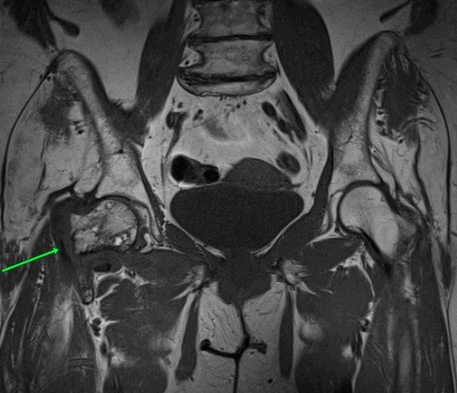

МРТ тазобедренных суставов.

МР-признаки базисцервикального перелома шейки правой бедренной кости с наличием зон инфаркта головки и шейки правой бедренной кости, синовита правого тазобедренного сустава, отека окружающих мягких тканей справа.